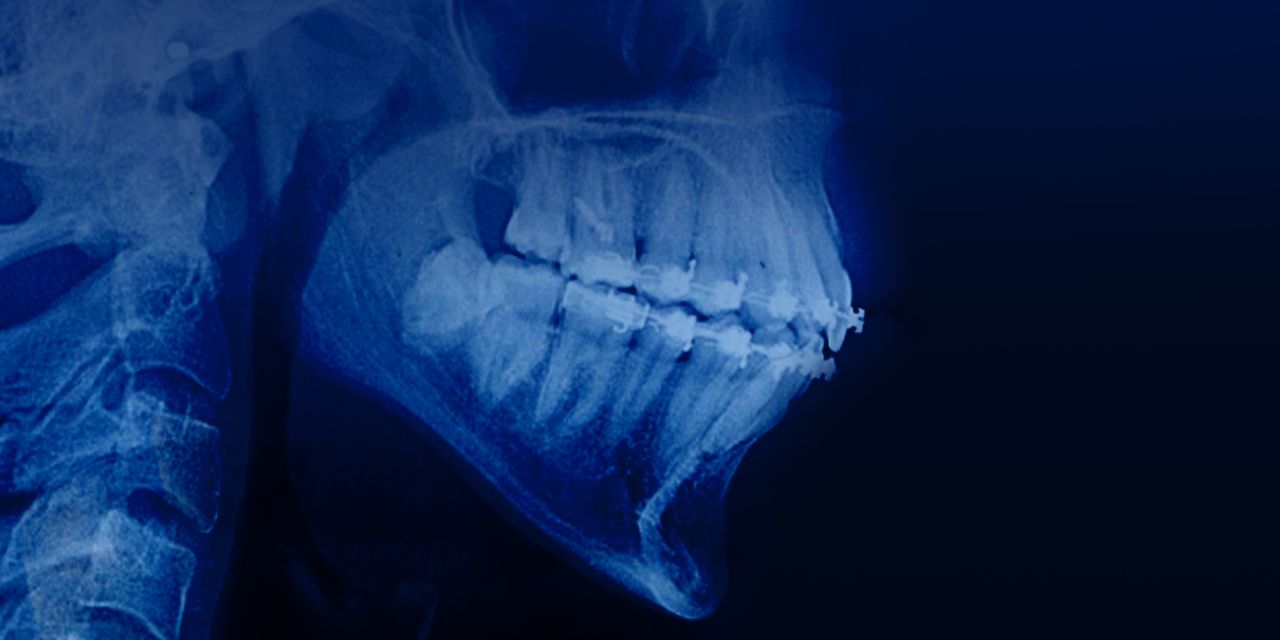

Ortodoncia en pacientes con patología periodontal y ósea

Lesson 3.Tratamiento ortodóntico en pacientes periodontales adultos

– Interrelación entre ortodoncia y periodoncia

– Los principios biológicos del movimiento dental ortodóntico en presencia de periodontitis